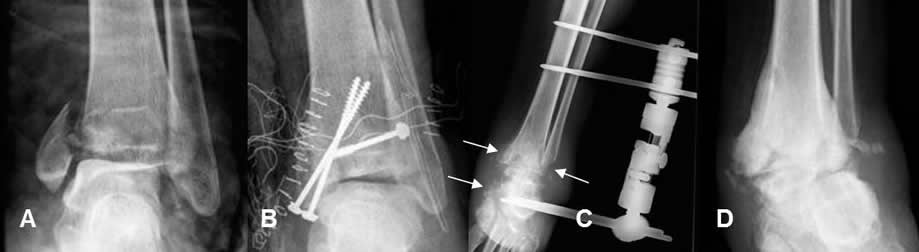

COMPLICACIONES DE LA FIJACIONES INTERNAS:

Fig 113 A. Infección del material.

A: Rx AP. Fractura desplazada del maleolo interno.

B: Rx AP. Reducción y fijación con tornillos.

C: Rx AP. Edema de tejidos blandos en el tobillo y osteolisis del calcáneo y ambos maleolos por osteomielitis, lo cual obliga a retirar el material y coloca tutor externo.

D: Rx AP. Como secuela queda artropatía neuropática hipertrófica y artrosis de la articulación.